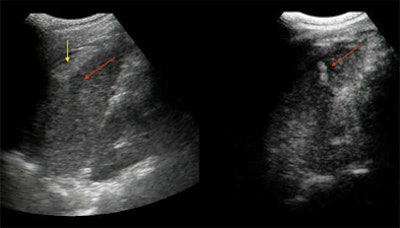

"In this patient with abdominal aortic aneurysm, baseline ultrasound shows the focal interruption of the aneurysm and left-sided resulting hematoma," Cusati said. "Contrast enhancement shows contrast extravasation.... In another image, "the contrast-opacified lumen of the aorta, after contrast extravasation, could be recognized as a hyperechoic jet, splashing through the aortic wall...."